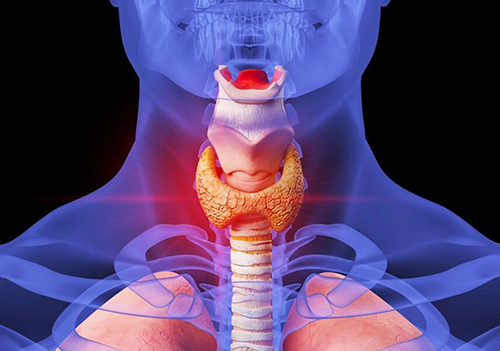

甲状腺是什么?

甲状腺位于颈前中正位置,由于形态像两面“护甲”,紧紧地保护着人体气管这一性命攸关的部位而得名“甲状腺”。其外形像一只蝴蝶,分左右两叶,中间由峡部相连。

正常甲状腺腺体质地柔软,犹如软橡皮一样,由两层包膜包围并固定于气管和环状软骨上,所以做吞咽动作时,甲状腺也随之上下移动。正常甲状腺重约25~30克,一般看不见外形。当甲状腺肿大或结节明显时才能见到。

甲状腺周围的血管神经非常丰富,且整个腺体内血流量极大,肿大时血流成倍增加。甲状腺的血供主要来源于一对甲状腺上动脉和甲状腺下动脉。甲状腺周围的淋巴管也极为丰富,淋巴液经滤泡周围的淋巴丛引流到气管、纵隔、喉前颈部淋巴结,所以甲状腺癌可沿淋巴管转移至上述淋巴结。【妇幼健康科普】